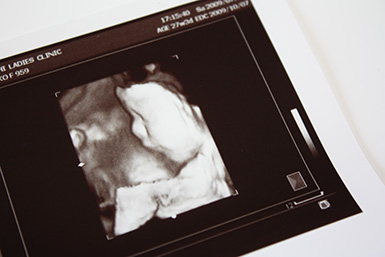

エコー写真の見方、ACやBPDの数字の意味は?

エコー写真を見ると、おなかの中にいる赤ちゃんの成長の様子がわかり、ある程度大きくなると性別を知ることもできます。また、エコー写真には赤ちゃんのサイズを表す文字がいろいろと書かれていますが、おもなアルファベットの意味は以下のとおりです。

- BPD……児頭大横径(頭の横幅)

- AC……腹部周囲長(おなかまわりの長さ)

- APTD……腹部前後径(おなかの前後の厚み)

- TTD……腹部横径(おなかの横幅)

- FL……大腿骨長(太ももの骨の長さ)